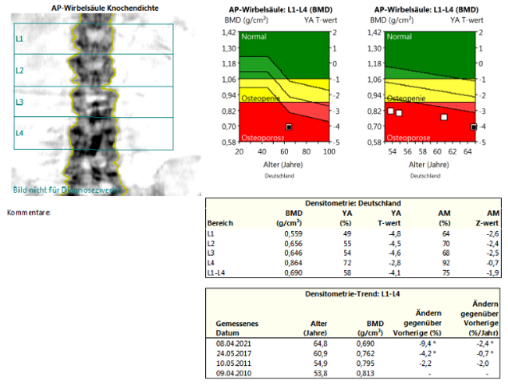

DXA + TBS:

Bei der Patientin liegt einerseits eine hochgradig reduzierte Knochenmineraldichte vor im Sinne einer sekundären manifesten Osteoporose mit multiplen atraumatischen Wirbelkörperfrakturen und andererseits zusätzlich eine

Osteomalazie. Die Ursache der Osteomalazie liegt in der Malabsorption, trotz hochdosierter Vitamin D Substitution liegt ein Mangel vor. Zudem wird zu wenig Calcium über den Gastrointestinaltrakt aufgenommen. Konsekutiv erhöht sich

Ursächlich für die ausgeprägte Osteomalazie bei dieser Patientin ist ein schwerer Mangel an Vitamin D3 und Calcium. Ein Marker der Osteomalazie ist die Erhöhung der Alkalischen Phosphatase. Somit steht eine ausreichende Substitution

Eine antiresorptive Therapie ist kontraindiziert bei Patienten mit Osteomalazie. Eine spezifische Osteoporosetherapie darf erst nach Normalisierung von Calcium, Parathormon und Alkalischer Phosphatase eingeleitet werden.

Aufgrund des sehr hohen Risikos und den aufgetretenen Spontanfrakturen unter antiresorptiver Behandlung, stellen eine Indikation für eine osteoanabole Therapie dar. Im Anschluss an diese Therapie ist jedoch eine

Konsolidierungstherapie zwingend erforderlich. Aufgrund der deutlich reduzierten Knochendichte und der anhaltenden Behandlungsindikation, würde die Patientin von einer Anschlussbehandlung mit Denosumab 60mg s.c. alle 6 Monate

profitieren.